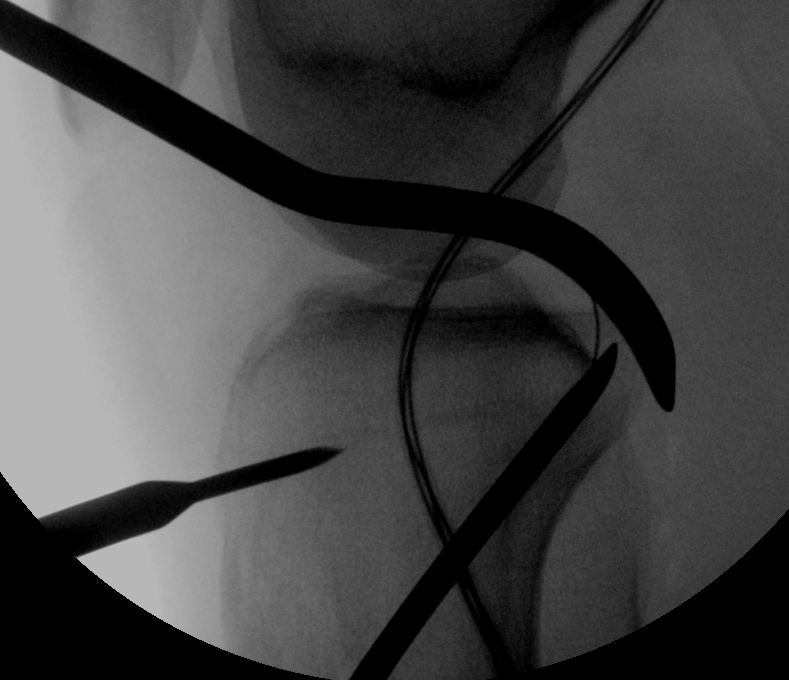

Tibial tunnel

- lateral arthroscopy portal

- small medial parapatellar approach

- insert PCL jig

- hooks over back of tibia

- check position on fluoroscopy

- pass beath pin

- drill 6 mm

- pass loop wire